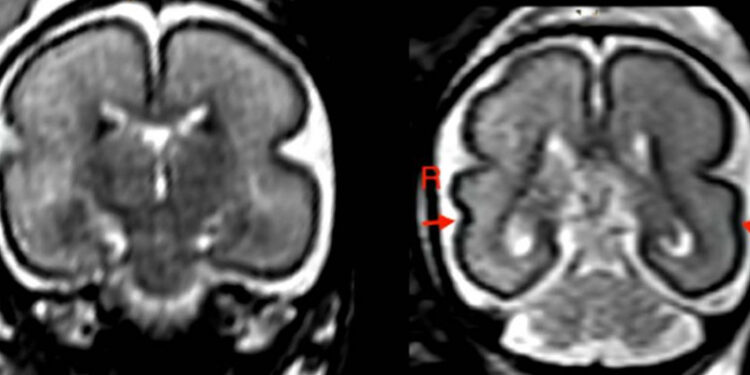

Beber en el embarazo, incluso poco, produce cambios en el cerebro del bebé

Estudio analizó resonancias magnéticas de 24 fetos de entre 22 y 36 semanas de gestación.

Redacción Ciencia, 22 nov (EFE).- El consumo de alcohol durante el embarazo, incluso en cantidades bajas o moderadas, puede modificar la estructura cerebral del bebé y retrasar su desarrollo. Esto lo descubrió un estudio de la Universidad de Viena.

La investigación, que se presentará la semana que viene en la reunión anual de la Sociedad Radiológica de Norteamérica (RSNA), analizó resonancias magnéticas realizadas a 24 fetos entre las semanas 22 y 36 de gestación. La exposición al alcohol de las madres se determinó mediante encuestas.

En los fetos expuestos al alcohol, la puntuación total de maduración fetal era significativamente menor que en los controles emparejados por edad. Además, el surco temporal superior (STS) derecho, que interviene en la cognición social, la integración audiovisual y la percepción del lenguaje, era más superficial.

Encontramos los mayores cambios en la región cerebral temporal y en el STS, dijo Greorg Kasprian, uno de los autores del estudio.

El investigador destacó que habían observado cambios cerebrales en los fetos incluso con niveles bajos de exposición al alcohol.

El retraso en el desarrollo del cerebro del feto podría estar relacionado específicamente con un retraso en la etapa de mielinización y una girificación menos marcada en los lóbulos frontal y occipital.

El proceso de mielinización es fundamental para el funcionamiento del cerebro y del sistema nervioso. Asimismo, la girificación se refiere a la formación de los pliegues de la corteza cerebral.